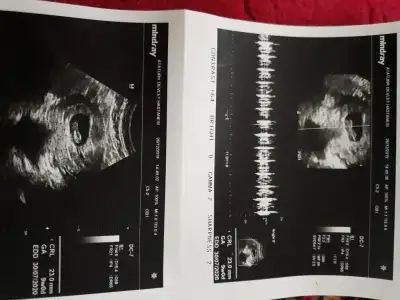

Merhabalar benim de ikili resimde vajinal diğer resim karından bakıldı.O zaman kız gibi değil mi

Sola yakın 6+3 usgeniz buna göre erkekMerhabalar benim de ikili resimde vajinal diğer resim karından bakıldı.O zaman kız gibi değil mi

Benim gönlümden geçen de erkek.bir kızım var ve ikinci çocuğum da erkek olsun isterim ama tabi ki Hayırlısı ne ise olsun.sadece iki tane alt alta olan resimler vajinadan bakıldı o yüzden bana kız gibi geldi dedim.tersi oluyordu ya ben yanlış mı anladım acaba .Ama artık bu hafta gitcem bakalım ne dicek doktorSola yakın 6+3 usgeniz buna göre erkekkese konumu her zaman tutmuyor nub teoriside bazen yanıltıyor pozisyondan dan yanılmalar oluyor cnm rabbim gönlünüzdekini nasip etsin

Vajinalsa kız canım ama dediğim gibi kese konumu tutmayada bilirBenim gönlümden geçen de erkek.bir kızım var ve ikinci çocuğum da erkek olsun isterim ama tabi ki Hayırlısı ne ise olsun.sadece iki tane alt alta olan resimler vajinadan bakıldı o yüzden bana kız gibi geldi dedim.tersi oluyordu ya ben yanlış mı anladım acaba .Ama artık bu hafta gitcem bakalım ne dicek doktor

Evet bakmistiniz ekleyeyim yine de buradan çok net değil sanki ama siz erkek gibi demiştinizTup de olsa nub nubturhayırlısı olsun sizin için ama kese tutmuyor genelde nuba baktımmı hatırlayamadım

Benimkinede bakarmisiniz vajinal ultrasonla bakildi

Vajinal solda buna göre sagda ve kız digeri 9 hafta olmaz kese konumu içinMerhabalar bende cinsiyetini.merak ediyorum bi tahmininiz var mi ?

1.resim karindan tek olan vajinal

Eki Görüntüle 2572005 sizce benim bebeğim ne tarafta kafam karişti bi tahmin de bulunurmusunuz acaba rica etsem tam 7 hafta günlük

Buna göre sagda karından bakıldıysa kızEki Görüntüle 2572005